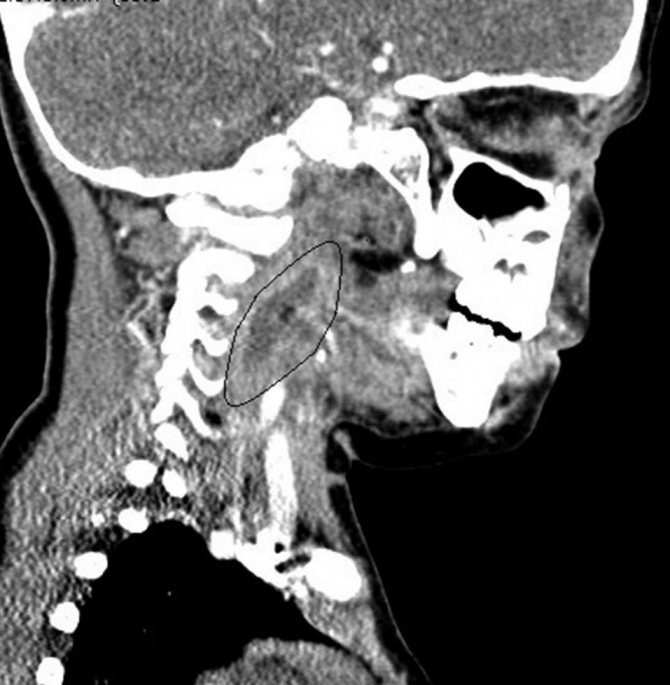

В некоторых случаях может потребоваться инструментальное обследование – УЗИ, КТ, рентгенография. Это необходимо для исключения развития новообразований и определения точной локализации воспалительного процесса.

Прежде чем поставить диагноз «паратонзиллярный абсцесс», необходимо провести дифференциальную диагностику со скарлатиной, дифтерией, злокачественными опухолями и аневризмой сонной артерии.